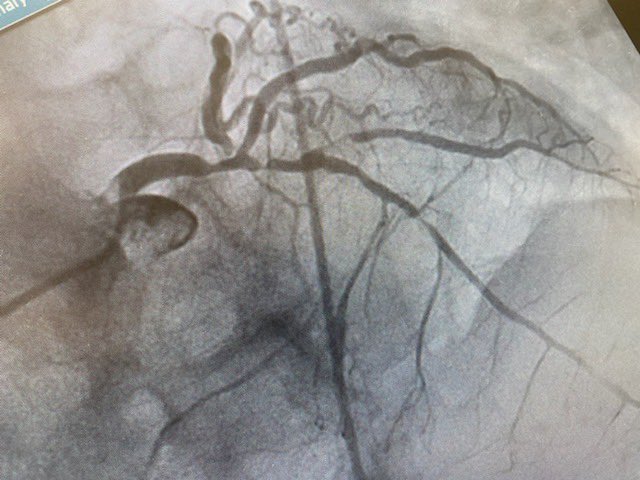

Anterior #STEMI #RadialFirst. Loving what I do @uvahealthnews

DrVal_Iz's tweet image. Anterior #STEMI #RadialFirst. Loving what I do @uvahealthnews